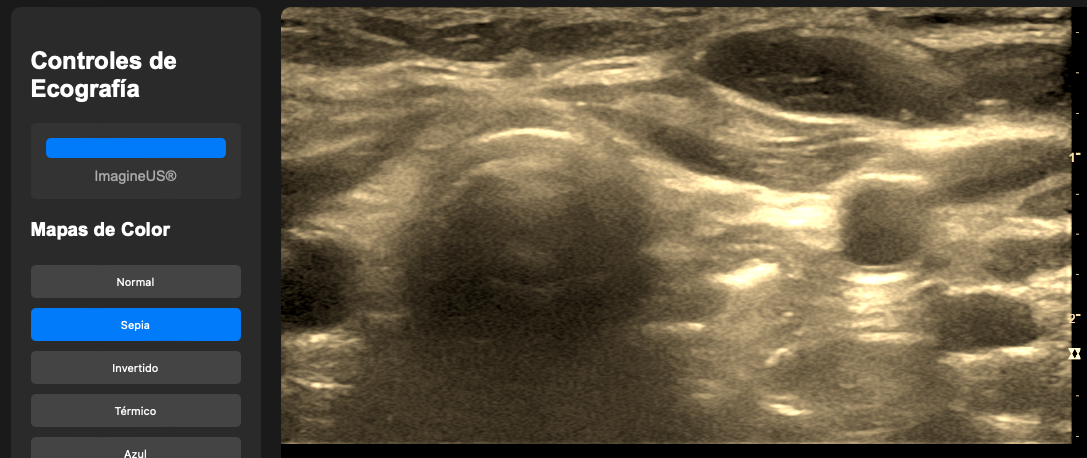

👉📟 Ir a Imagineus®.

Esta intefaz de usuario, la podras encotnar en el modulo del curso II: Parametros nivel avanzado ( pronto)